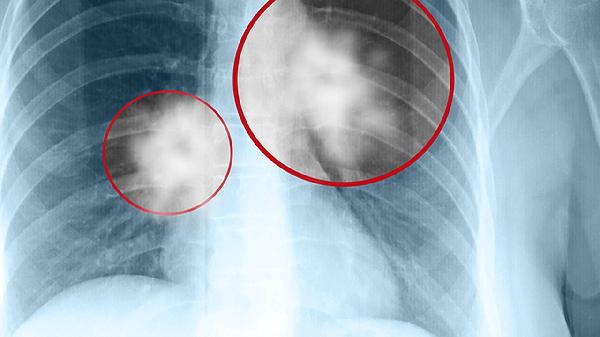

2、肿瘤分期:肾癌的分期是影响预后的关键因素。I期和II期肿瘤局限于肾脏,通过手术切除后治愈率高。III期肿瘤可能侵犯周围组织或淋巴结,治疗效果相对较差。IV期肿瘤已发生远处转移,治疗难度大,生存时间较短。